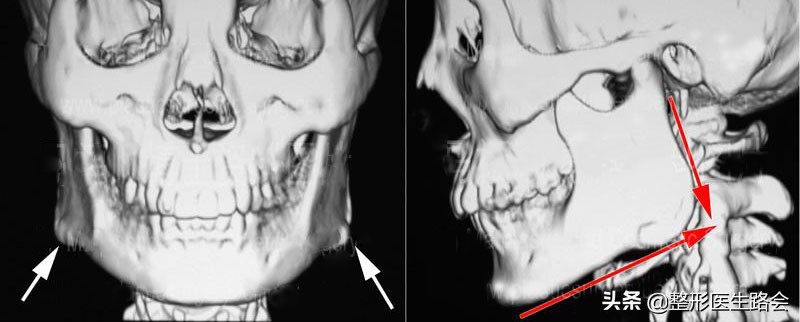

前些天门诊来了一位“国字脸”的求美者,想改脸型的需求特别迫切,面诊之后发现她的下颌角比较肥大,而且有呈直角的趋势,需要通过下颌角手术来矫正。

为了术后正面看起来更自然一些,因此还需要结合皮质骨切除术。

下颌角外翻、肥大